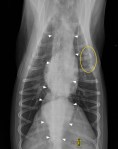

Latérale droite